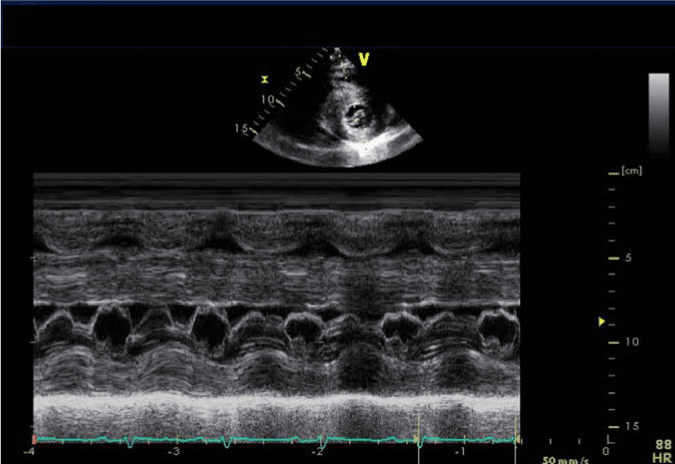

EKG showed sinus rhythm with left axis deviation low voltage QRS complexes and poor R wave progression (Figure 1).   A 2 D Echocardiogram obtained on day 3 showed small left ventricular (LV) cavity, with thickened left and right ventricular walls (Movie Clip 1 and 2), systolic anterior motion of the anterior leaflet of the mitral valve (SAM) (Figure 2), enlarged septum with septum measuring 31 mm with LV outflow max gradient of 34 mm Hg , mean gradient of 19 mm Hg and velocity of 295 cm/sec, normal left ventricular wall motion with speckling and increased echogenicity , estimated LV ejection fraction (LVEF ) of 65-70%, abnormal relaxation pattern, normal sized right and left atria and a small pericardial effusion (Figure 3). LV Strain imaging showed Global Longitudinal strain of -7.47% (normal -18%) (Figure 4) with regional strain values greatly reduced in the basal and mid LV, yet preserved at the LV apex.

Figure 2. Parasternal short axis (PSAX) with M- mode echocardiography showing systolic anterior motion of the anterior leaflet of the mitral valve.